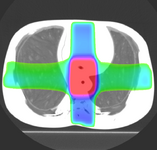

Image:PETCTFusion.png| [[Modules:PETCTFusion-Documentation-3.6 |PETCTFusion]] (Wendy Plesniak) | Image:PETCTFusion.png| [[Modules:PETCTFusion-Documentation-3.6 |PETCTFusion]] (Wendy Plesniak) | ||

PETCTFusion (Wendy Plesniak)